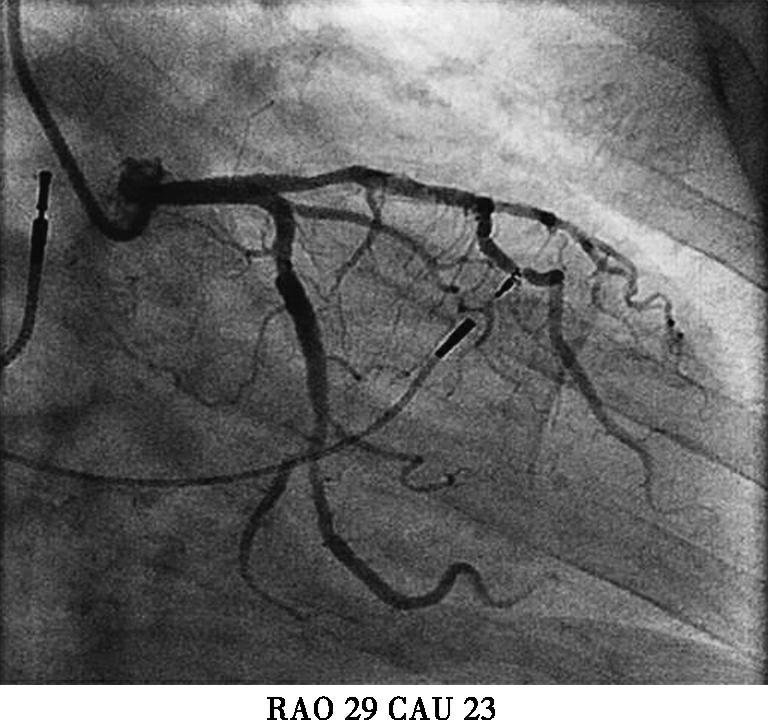

本例患者虽然有高血压、糖尿病等冠心病危险因素。起搏器电极植入后立刻发生的胸痛考虑与心绞痛关系不大,且患者未出现心电导联ST-T变化,胸痛原因主要考虑:起搏电极导致冠脉损伤?起搏电极刺破右室?遂台上决定立即行冠脉造影(图3);多个投照体位均可见起搏电极螺旋尖端触及前降支,因此决定行前降支血管内超声(IVUS)检查,结果于电极接触部位,血管8点钟方向可见强回声,距离血管外膜小于1mm;综合判断起搏电极损伤血管外膜导致胸痛的可能性大;随后进行电极重新植入,并再次造影排除起搏电极穿透冠脉可能,电极具体位置及冠脉造影见图4,心室起搏参数(阈值0.8V,阻抗670Ω,R波10.0mv)。患者症状完全消失,于导管室留观30分钟,复查心脏超声,心包内未见积液,排除起搏电极刺破右室可能,转回病房。

图3初次植入心室电极后冠脉造影